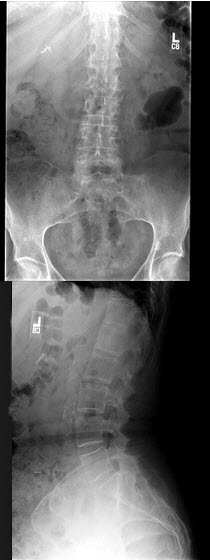

17、单项选择题

男,6岁,来自干旱地区,腰背疼痛四肢关节酸痛,结合图像,最可能的诊断是()

A.氟骨症

B.畸形性骨炎

C.石骨症

D.髋关节结核

E.甲状旁腺功能亢进